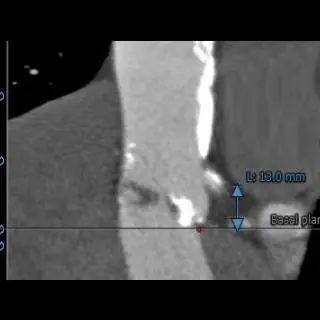

主动脉根部测量

冠脉高度、瓣叶长度测量

瓣环上多平面测量

左右冠高度合适,冠脉可见局部钙化,左冠瓣长度>冠脉开口与瓣叶附着缘距离。